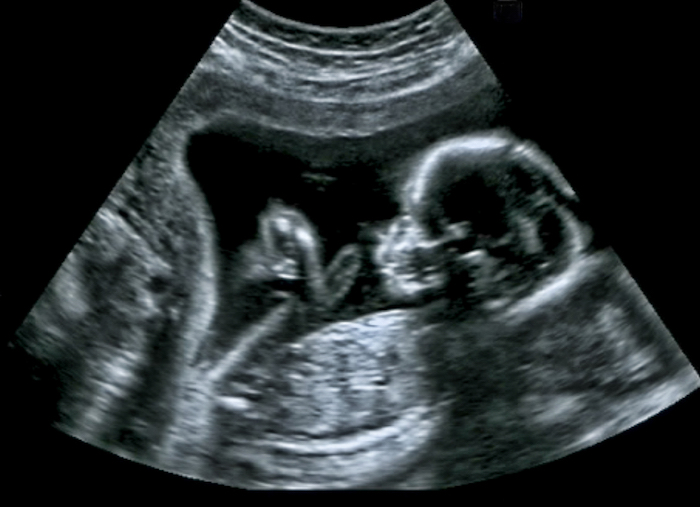

Je suis enceinte de 25SA de mon premier bébé. Lors de mon RDV, la sage-femme m’a pesée et n'a pas été super positive car j'ai pris au total 11kg depuis le début de ma grossesse, dont 6kg pendant entre mes deux RDV (mi janvier-mi février).